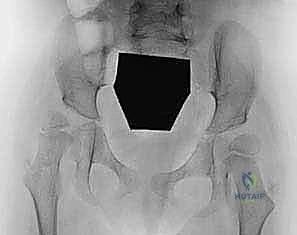

التشخيص الدقيق: المعيار الذهبي في عيادة الأستاذ الدكتور محمد هطيف

يبدأ العلاج الناجح بتشخيص دقيق لا يقبل الخطأ. يتمتع الأستاذ الدكتور محمد هطيف بخبرة تتجاوز العشرين عامًا في تقييم حالات العظام المعقدة للأطفال. يشمل التقييم:

- الفحص السريري الشامل: استخدام اختبارات طبية متخصصة مثل "اختبار توماس" (Thomas Test) لتقييم تشنج العضلة الحرقفية القطنية، واختبار زاوية التبعيد لتقييم العضلات المقربة.

- تحليل المشي (Gait Analysis): مراقبة دقيقة لكيفية حركة الطفل وتوزيع وزنه.

- الأشعة السينية (X-rays): لتقييم وضعية رأس عظمة الفخذ داخل التجويف الحُقي وحساب "مؤشر رايمرز" (Reimers Migration Percentage).

- الأشعة المقطعية ثلاثية الأبعاد (3D CT Scans): في الحالات المتقدمة، تُستخدم لتقييم التشوه العظمي بدقة متناهية قبل التخطيط للجراحة.